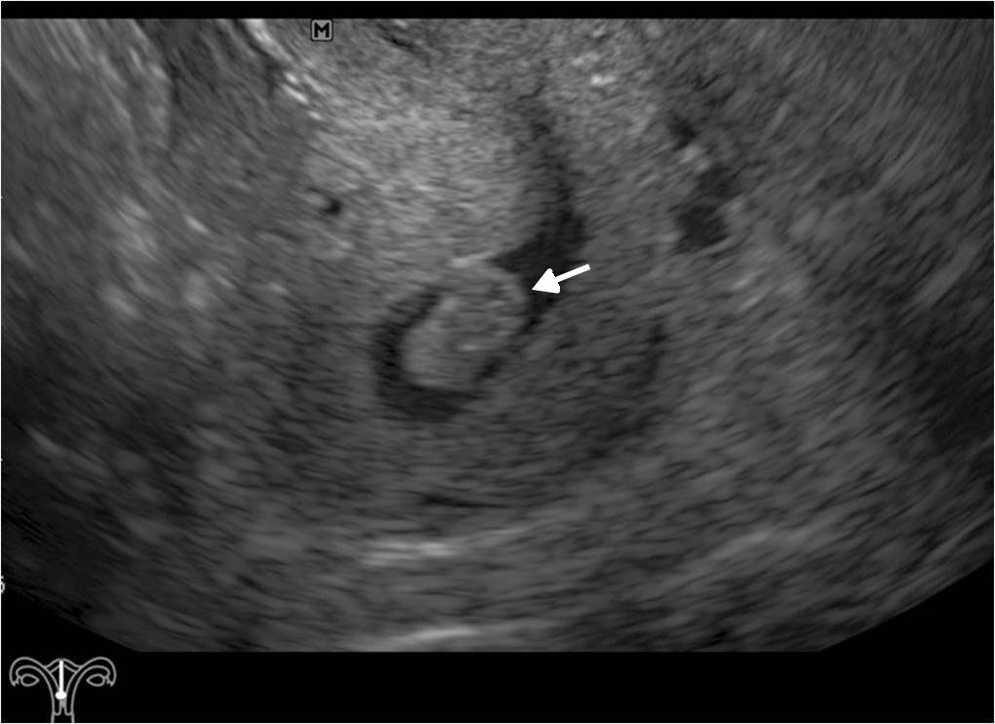

Sangrado ginecol??gico de la menopausia

La mayor??a de las consultas ginecol??gicas en pacientes peri y posmenopa??sicas se debe al sangrado ginecol??gico11 (figs. 5 y 6). En estos casos, la ecograf??a ginecol??gica endovaginal constituye la primera opci??n de estudio, debido a que visualiza excelentemente el endometrio, tiene buena tolerancia y un alto valor predictivo negativo para el carcinoma endometrial (si se reconoce el endometrio fino)12.

Los principales diagn??sticos diferenciales incluyen atrofia, hiperplasia, p??lipos y carcinoma endometrial, entre otros11.